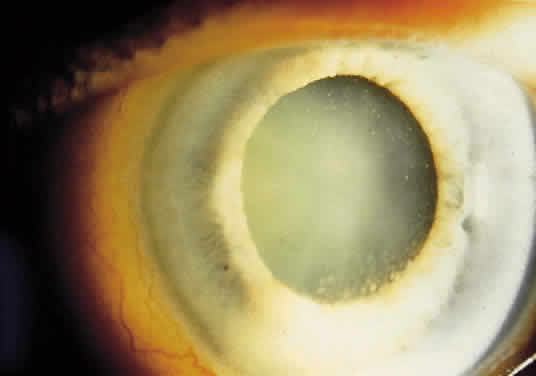

External examination may reveal diffuse episcleritis, scleritis, or orbital inflammatory disease. Mild to moderate anterior segment cellular reaction is common and either granulomatous or fine keratic precipitates typically are present 10,16,17(Fig. 1). A hypopyon typically does not develop.8 The intraocular pressure may be low, even in the absence of retinal detachment; however, elevated intraocular pressure secondary to anterior segment inflammation also may occur. Concurrent herpesvirus infection of the cornea with dendritic or stromal keratitis is not a typical feature of ARN syndrome in healthy individuals, although it has been described in patients with HIV infection.18,19 One case of simultaneous HSV type 1 keratitis and ARN was reported in a patient with Ramsay Hunt syndrome.20,21